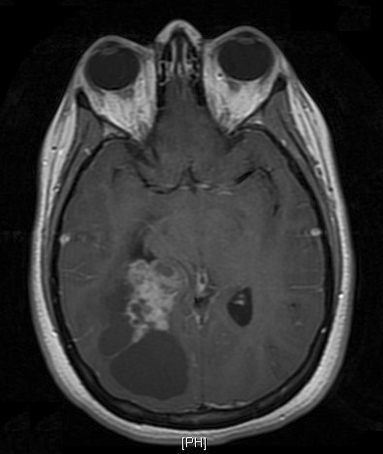

Pathology of the Case: MRI shows a large mass with the more solid component located in the lateral ventricles and the cystic component protruding into the cortical area. The solid area is enhanced (Panel A). On low magnification, the lesion has alternating area of high and low cellularity (Panel B) with scattered calcifications in some of the sections. Medium and high magnification demonstrates perivascular coronary arrangement of cytoplasmic processes (Panel C, D, and E). The nuclei are bland and mitotic figures are not readily seen. Randomly scattered brown pigment containing cells are found in multiple areas of the tumor (Panel F, G, and H). Scant lipidized cells with enlarged nuclei (Panel I) are also present. The tumor cells are strongly positive for glial fibrillary acidic protein (GFAP) (Panel J and K) and S100 protein but are negative for epithelial membrane antigen (EMA), neurofilament proteins, and NeuN. The overall Ki67 labeling is low but focal small areas (about the size of one high power field) has increased labeling. The pigment appears to be melanin on microscopic examination. These pigments are positive with Fontana-Masson stain (Panel L) but negative for Prussian blue stain for iron (Panel M). These features confirmed that these are melanin pigments. The pigment granules are positive for periodic acid-Schiff reaction (N), negative for Ziehl-Neelsen (acid fast) stain..

Microscopically, the histology of ependymoma can be quite variable and be easily confused with other gliomas. In essence, there are three major histologic features in ependymoma and most tumors contain a mixed features. The four features are perivascular radial arrangement of epdnymomal cells, isomorphic nuclei, ependymal rosettes or ependymal canals.

The diagnostic pattern of ependymoma is best visualized with very low magnification under the microscope. Similar to astrocytomas, the cytoplasm membrane cannot be discerned. The cells are poor in cytoplasm and the perivascular cell processes taper to a point around the blood vessels. Nuclear-free mantles form cuff like spaces around the vessels is an important diagnostic feature. These structures are also known as pseudorosettes. The cellularity in the cellular can be quite variable. The thickness of the perivascular paucinuclear zone can also be quite variable. As a result, they may be mistaken as astrocytoma easily and in the case of pediatric brain tumors as pilocytic astrocytomas.